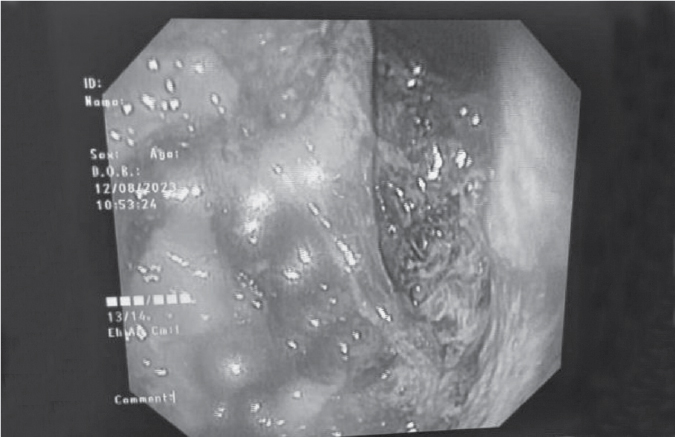

Upper gastrointestinal endoscopy revealed esophagitis with necrosed gastric mucosa (Fig. 2).

Figure 2. Upper gastrointestinal endoscopy of the patient showing esophagitis with necrosed gastric mucosa.